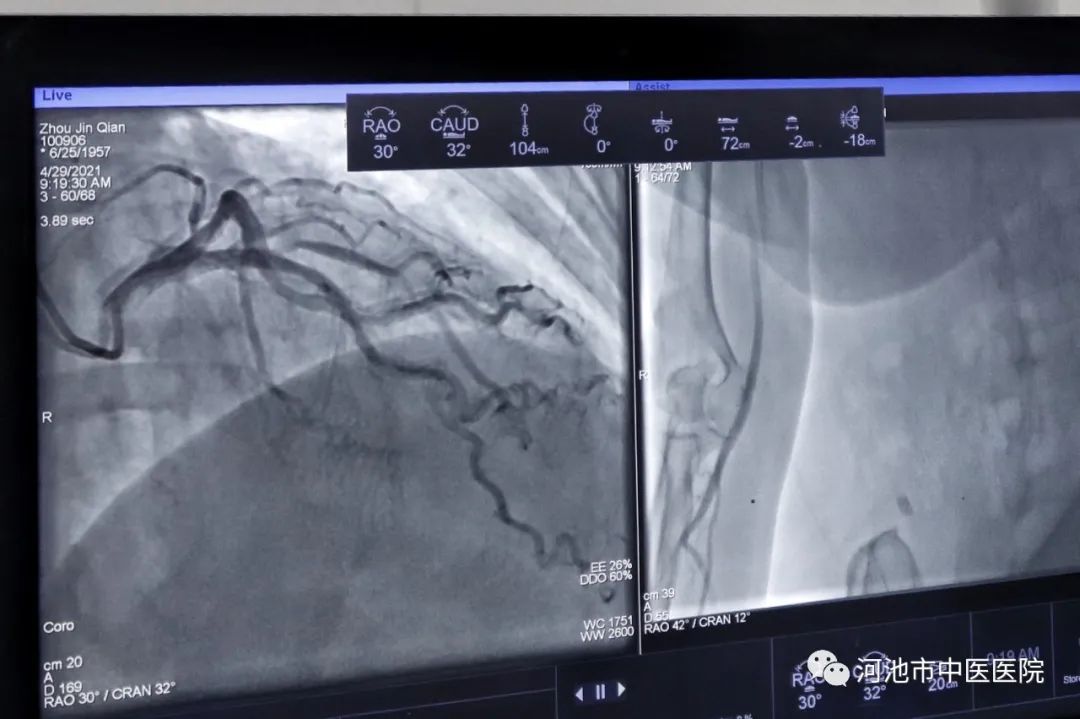

患者术中心血管数字显影图像。

冠状动脉造影是一种常规的微创检查,通过穿刺桡动脉或者股动脉,将造影导管送至冠状动脉开口,在造影导管内加压注射造影剂,在X线透视下观察冠状动脉的形态、血流情况以及有无畸形、有无狭窄,评估冠脉狭窄程度及病变范围,评定是否需要进行介入治疗、搭桥手术治疗或者保守性治疗,或作为外科冠状动脉搭桥术和内科冠状动脉介入治疗术前评价及术后复查评估的有创检查。